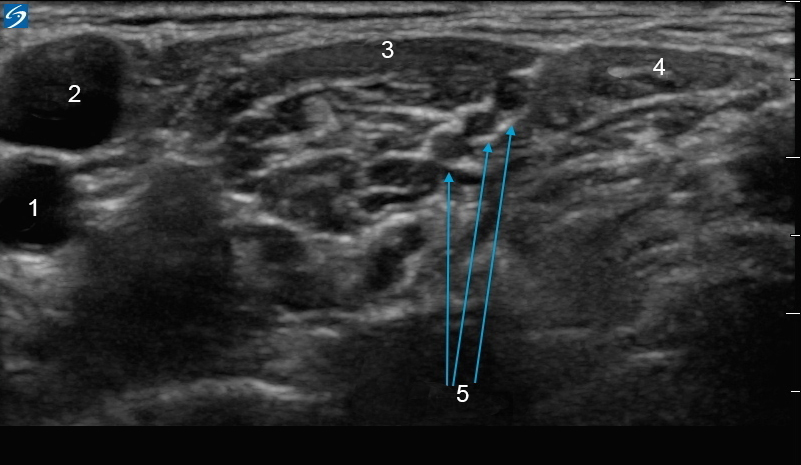

Image 1 : X-Porte : bloc interscalénique

1. Artère carotide

2. Veine jugulaire

3. Scalène antérieure

4. Scalène moyen

5. Nerfs